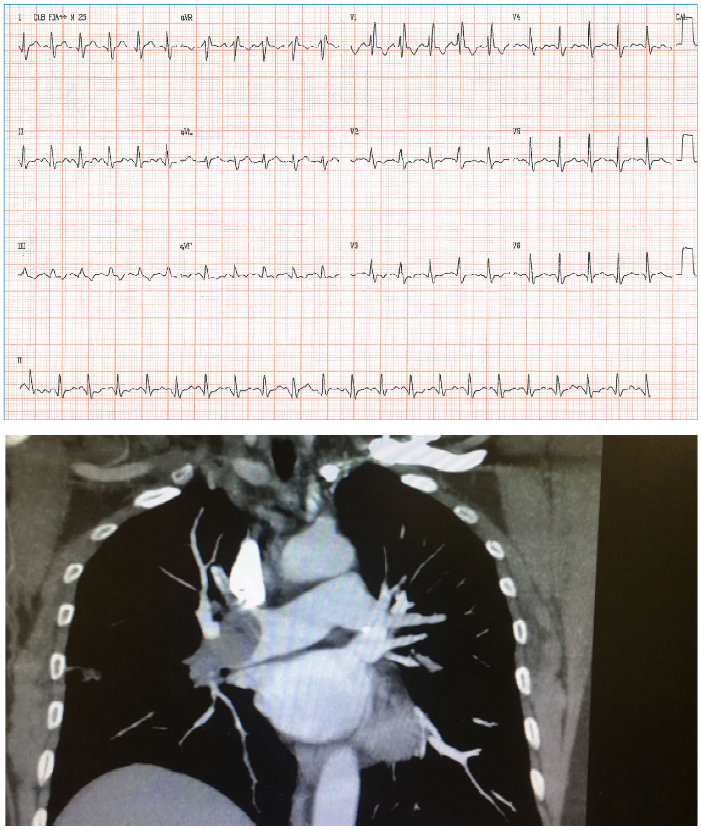

Edileuza, 64 anos, tabagista e diabética, procura serviço de pronto atendimento com dor precordial há 2 horas e PA = 149x96 mmHg. A paciente realiza eletrocardiograma, conforme imagem a seguir:enunciado 1960520-1

Após a realização do eletrocardiograma, o plantonista institui algumas condutas terapêuticas. Porém, após a utilização de uma das medicações, o quadro de Edileuza evolui para hipotensão acentuada, mal-estar generalizado e sintomas de baixo débito, sem rash cutâneo ou angioedema. Qual medicação poderia justificar o quadro dessa paciente?

Sr. JG, 60 anos, procura o serviço hospitalar com falta de ar e dor torácica iniciada há 40 minutos. Referiu que, na véspera, começou a se sentir mal e esteve no mesmo hospital, quando foi examinado e realizou radiografia de tórax e eletrocardiograma. Na ocasião, os médicos lhe disseram que não encontraram anormalidades relevantes e deram alta a ele, que foi para casa. O paciente possui histórico de tabagismo crônico. Exame físico: FC = 134 bpm, FR+ 36irpm, PA = 89x58 mmHg, Oximetria = 85%, sudorético. AR = murmúrio vesicular fisiológico, sem ruídos adventícios; ACV: bulhas rítmicas e fonéticas. Seguem abaixo as imagens do ECG e TC de tórax.

enunciado 1960519-1

Qual a conduta CORRETA para esse paciente?